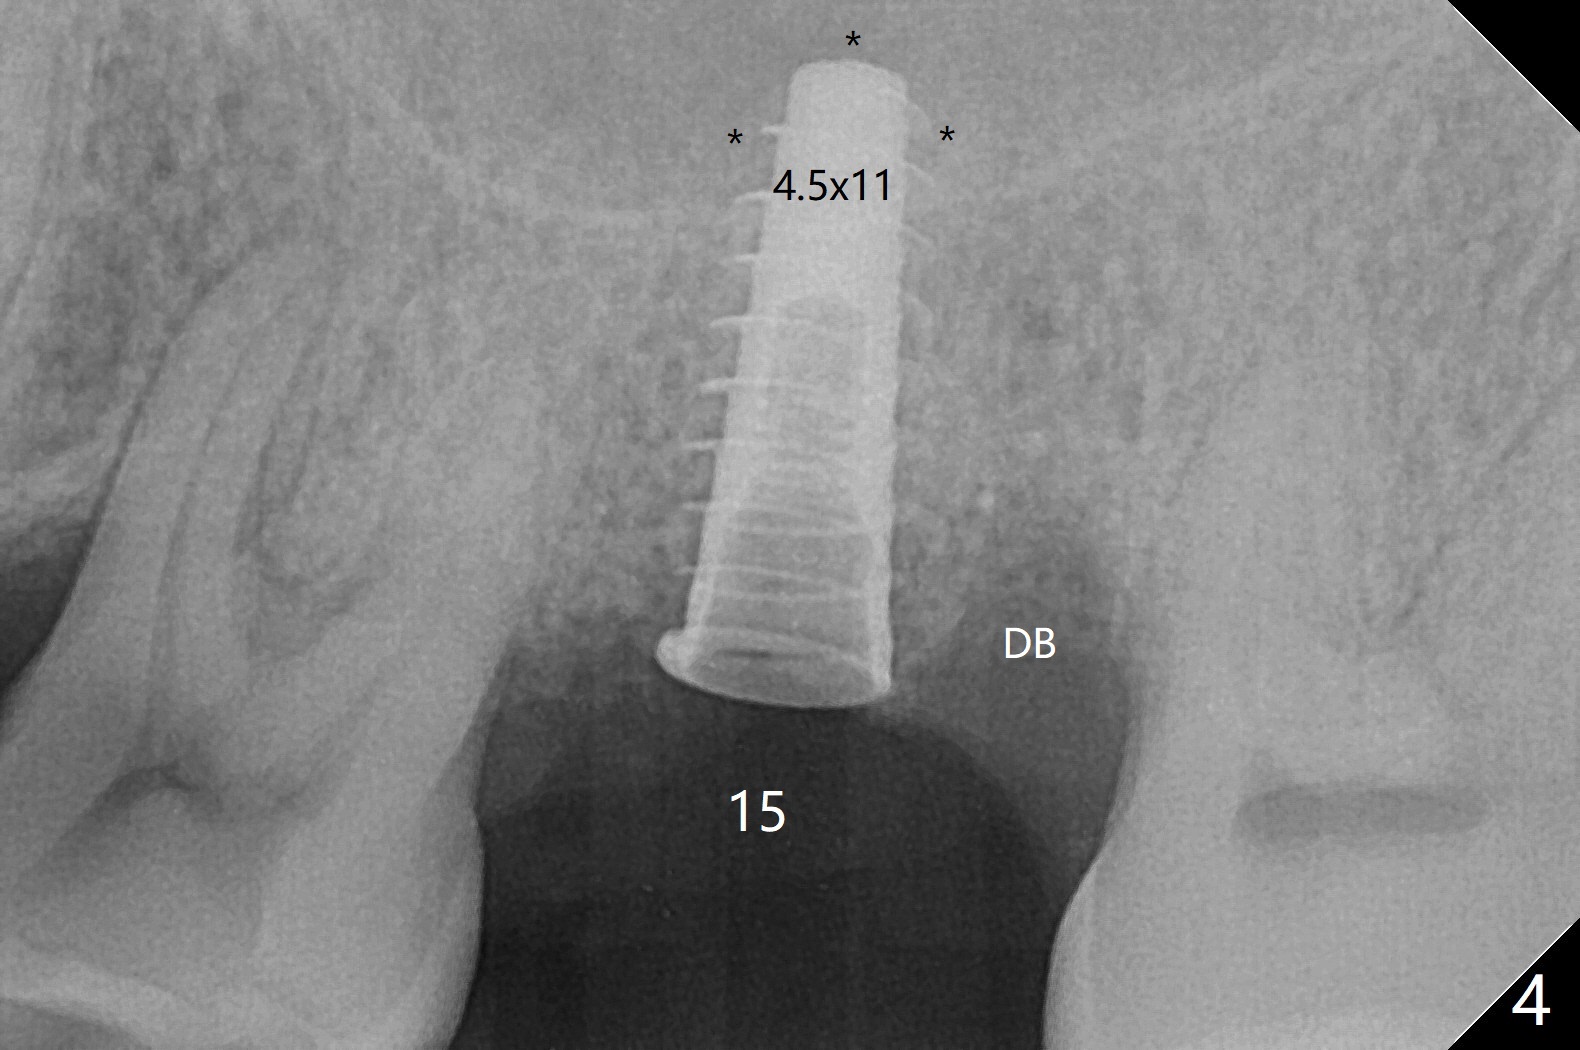

The tooth #2 has severe distobucal (DB) infection before and after extraction (Fig.1 *); sinus lift is done with 4.5x11 mm dummy implant using guide. After placing bone graft into the sinus and the osteotomy (Fig.2 black *), a 5x9 mm implant is placed with >30 Ncm. Second round of bone graft is placed around the implant, including DB defect (white *). Then a 5x4(2) mm pair abutment is placed, followed by the third round of bone graft (Fig.3 *). Finally an immediate provisional is fabricated to keep the graft in place. The implant is loose nearly 4 months postop.

At #15, the sinus floor is initially perforated with modified drill sequence. With placement of PRF and bone graft in the osteotomy, the same 4.5x11 mm dummy implant is inserted to start sinus lift (Fig.4 *). When the dummy implant is removed, more bone graft is placed into the osteotomy and pushed into the sinus with the 5x11 mm final implant (Fig.5). Second round of bone graft is placed next to the implant before placing a 4.5x4(2) mm abutment, but the latter appears not to be seated completely, as indicated by the arrowhead. After use of 6 mm profile drill, a 4.5x4(3 (cuff)) mm abutment is able to be seated apparently completely without a gap (Fig.6 <). The third round of bone graft (Fig.6 *) is placed around the abutment to make sure that the underlying implant is fully covered to reduce periimplantitis in the future. The bone graft around the abutment disappears most coronally, while that around the implant remains 4 months postop (Fig.7). The implant is stable.